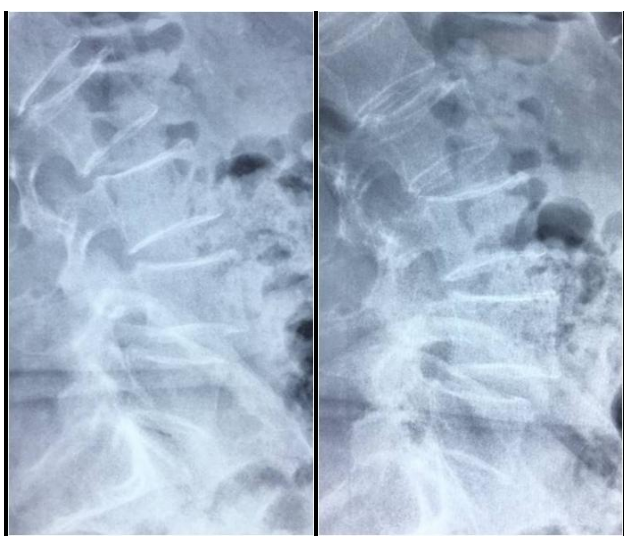

徐XX,女,66岁。

主诉:腰疼及左下肢疼痛麻木半年,加重3个月。

查体:L4-5棘间及椎旁压痛,左下肢直腿抬高试验50度阳性,双下肢肌力肌张力正常。

图1 术前X线片